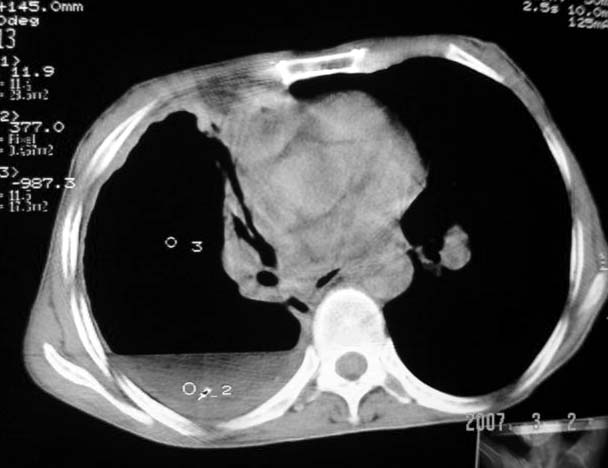

以下是引用dyqct在2007-3-2 22:04:00的发言:[br]考虑:1、右侧毁损肺伴支气管胸膜瘘(多条支气管与胸腔相通、液气胸);[br] 2、左肺浸润型肺结核。[br][br][br][br]